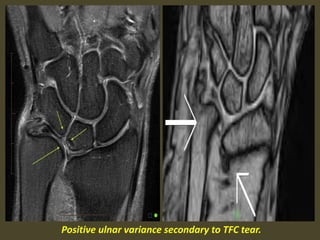

Positive ulnar variance secondary to TFC tear.

TFCC 1B tear (arrow) on coronal T1-WI (B) and coronal FS T2-WI (C).

Negative ulnar variance secondary to TFC tear.